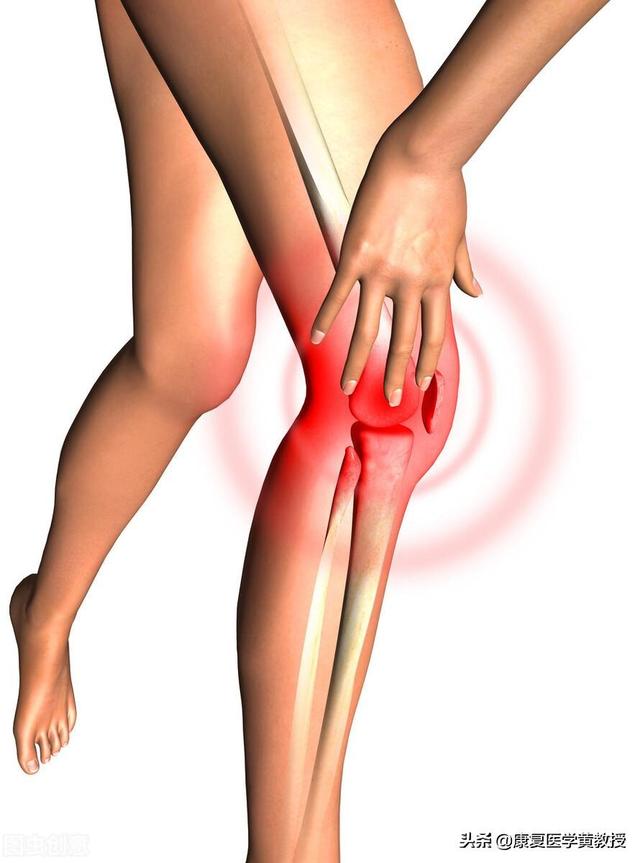

初期の変形性関節症患者は、しばしば以下のような症状を示す。膝裏の張り。であったろう。関節の弱さ特に、次の試合がある場合は。弱った足を叩くこの病気の症状として、しゃがんだ時に明らかに関節がポキポキと鳴り、痛みを伴う患者もいる。病状が重くなるにつれて、患者さんの症状はより重くなり、一部の患者さんでは徐々に階段の上り下りや平地を歩くときに関節が痛む。さらに重症になると、安静時にも関節痛が出現し、著しい痛みを伴うこともある。関節可動域障害および関節の変形。

変形性膝関節症の場合、女性には膝関節のレントゲン検査や膝関節の磁気検査をして、関節腔の軟骨がどのような状態なのか、最終的にどの程度の骨棘が形成されているのかを明らかにすることをお勧めします。その方が、患者さんが科学的な治療を行うのに役立つと思います。

炎症のために、特に癒着が起こりやすく、高齢者はしばしば膝関節のこわばりを感じ、体を動かすとポキポキと音がしたり、摩擦音がしたりする。